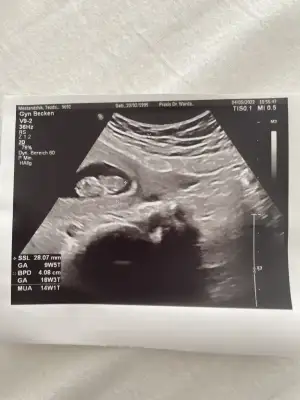

Merhaba burda 12 haftalıktı hala cinsiyet göremedi doktorlar ben de bi tahmininizi alabilirim :) teşekkürler şimdiden. Pasha22 Pasha22

Eklentiler

• IMG_20220429_150347.webp

IMG_20220429_150347.webp

46,7 KB · Görüntüleme: 92